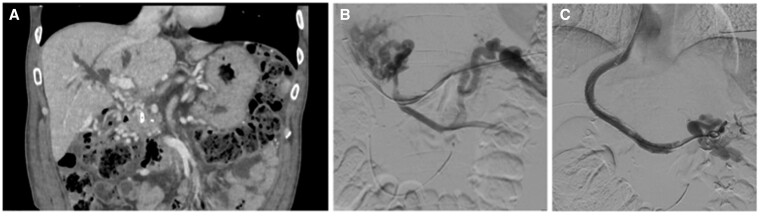

Transjugular intrahepatic portosystemic shunting (TIPS) is an established strategy for the management of complications of portal hypertension. Endoprosthetic infection ("endotipsitis") is a rare but serious and difficult-to-treat complication of TIPS placement. Here we report the occurrence of an infected thrombus complicating TIPS placement in a patient with extra-hepatic portal vein obstruction, recurrent variceal bleeding and portal biliopathy accompanied by recurrent cholangitis. Infected thrombotic material within TIPS could be removed only by employing rotational thrombectomy. This procedure revealed the presence of a biliary fistula which carried pathogens in the systemic circulation. The multiple episodes of sepsis did no longer recur following exclusion of the biliary fistula. This case highlights the possibility to use rotational thrombectomy for the management of complex cases of TIPS dysfunction.